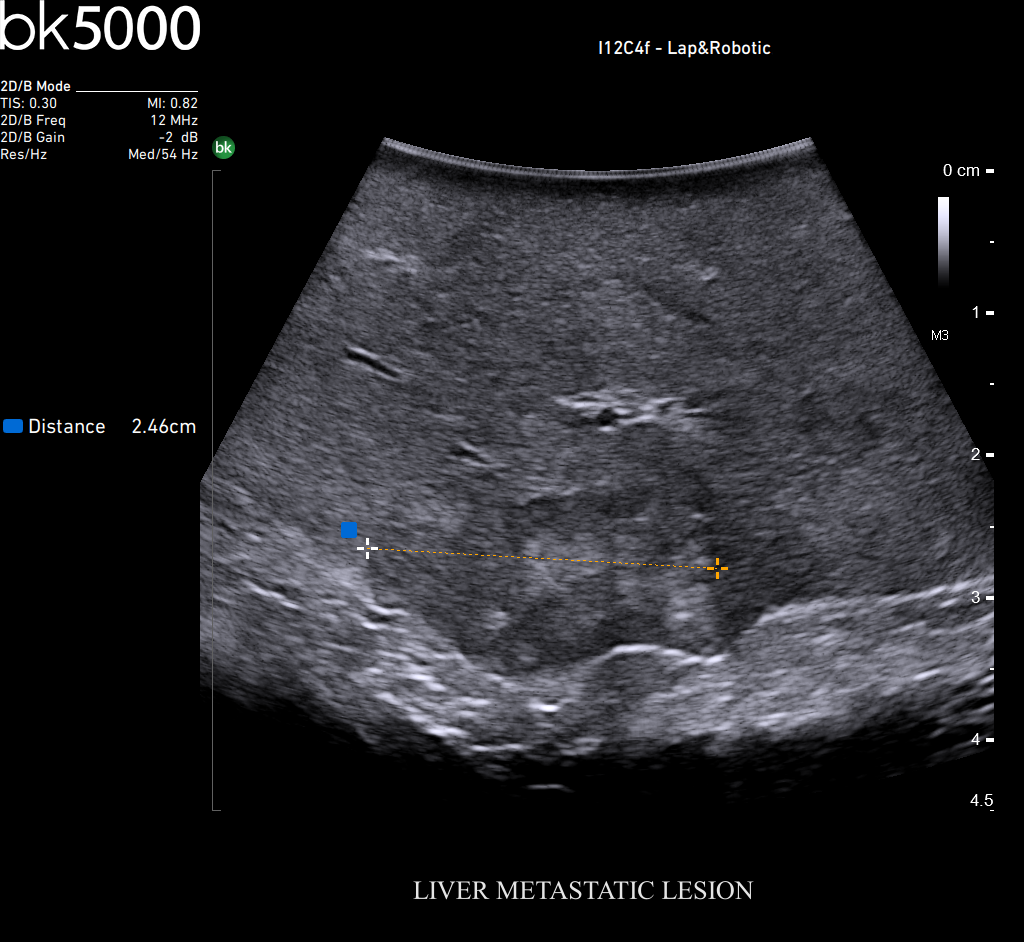

Ultrasound can advance intraoperative surgical procedures by helping you navigate and identify lesions and anatomical structures in real-time. This is particularly important as the data obtained from a preoperative CT or MRI scan can be outdated at the time of surgery.

The bk5000 surgical system provides the highest quality images that allow you to clearly see the margins of a lesion and to determine the best course of action. Using advanced graphics processing technology, this powerful system provides immediate, auto-optimized images that allow you to see the information you need, faster.